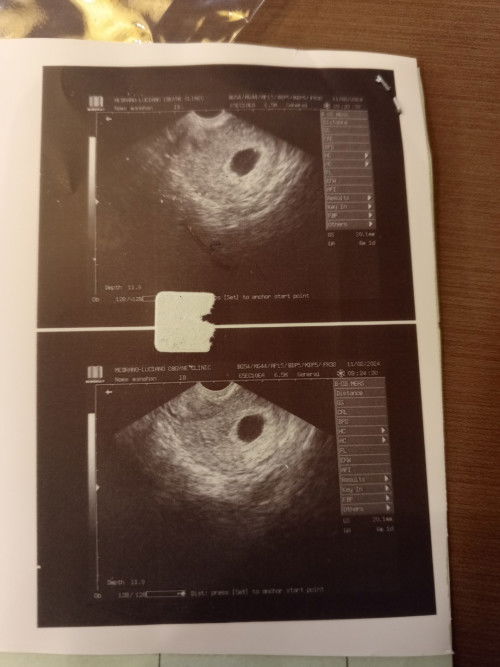

6weeks Gestational Sac only

Common po ba sa 6weeks na dipa agad nakikita fetal pole? any advice po mga momshie. Tia

Spotting @ 7weeks but suspected blighted ovum.

7weeks preggy via tvs. Pero suspected blighted ovum kaya need mag follow up after 2weeks. Pero ngaun nag i-spotting ako ng light brown. Need na kaya mag pa TVS ulit kahit 1week plng ung nkakalipas nung nagpa TVS ako?